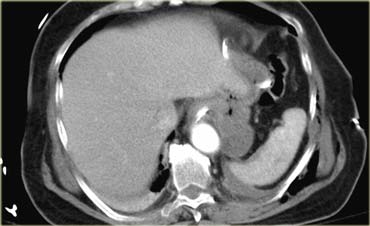

Trước tiên hãy quan sát các hình ảnh bên trái của bệnh nhân bị chấn thương gan.

Mô tả các dấu hiệu hình ảnh.

Các dấu hiệu bao gồm:

- Mũi tên xanh lá: vùng giảm tỷ trọng hình bầu dục phù hợp với tụ máu

-

Mũi tên vàng: vùng giảm tỷ trọng hình tuyến tính phù hợp với đường rách.

Lưu ý rằng đường rách này đi qua nhánh trái của tĩnh mạch cửa - Mũi tên xanh dương: vùng giảm tỷ trọng mờ, ranh giới không rõ phù hợp với dập gan

- Dịch quanh gan

- Gần như có sự đứt ngang hoàn toàn của gan, nhưng cả hai thùy đều còn ngấm thuốc, cho thấy nguồn cung cấp mạch máu vẫn còn bình thường.